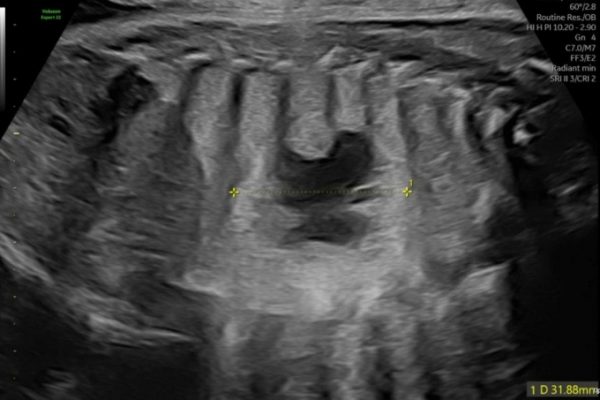

Thạc sĩ, bác sĩ chuyên khoa I Nguyễn Phương Thảo, thuộc chuyên khoa Y học bào thai tại Phòng khám Đa khoa Tâm Anh Quận 7, đã chẩn đoán một trường hợp thai nhi mắc phải tình trạng tăng sinh tuyến dạng nang ở phổi, hay còn gọi là dị tật nang tuyến phổi bẩm…